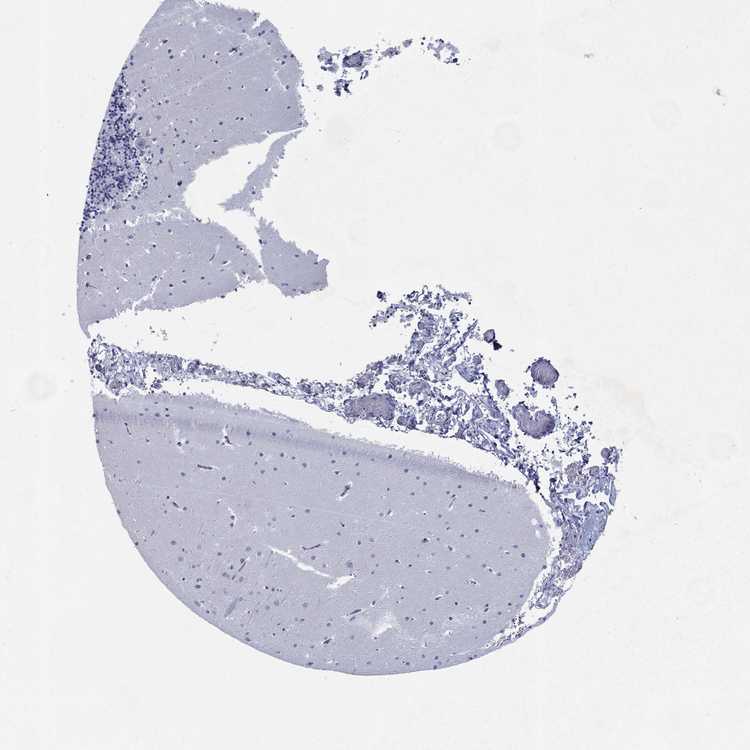

CEREBELLUM - Antibody stainingi

Antibody staining in the annotated cell types in the current human tissue is reported as not detected, low, medium, or high, based on conventional immunohistochemistry profiling in selected tissues. This score is based on the combination of the staining intensity and fraction of stained cells.

Each image is clickable and will lead to virtual microscopy that enables deeper exploration of all samples and also displays staining intensity scores, fraction scores and subcellular localization as well as patient and tissue information for each sample.

Antibody HPA076656

Purkinje cells Not detected

Cells in granular layer Not detected

Cells in molecular layer Not detected